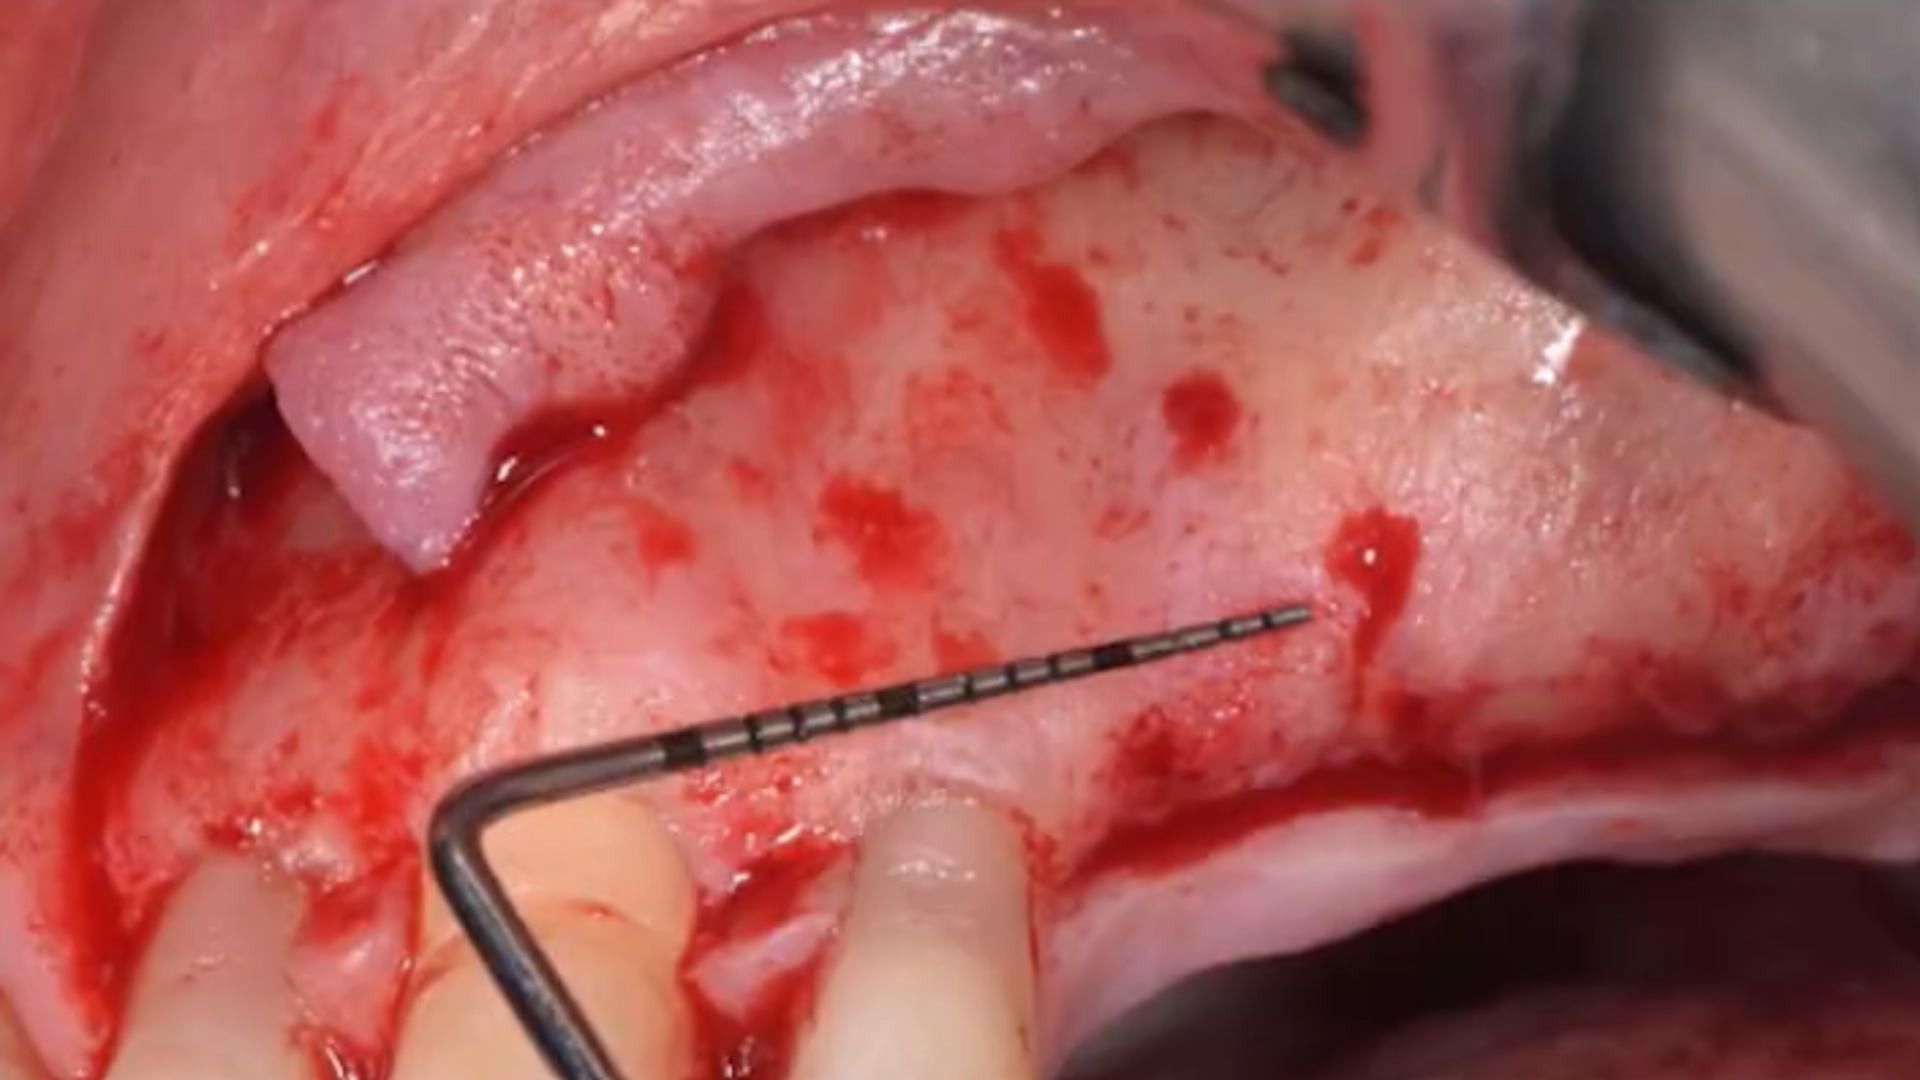

The evolution of the Lateral Approach: Lateral Window and Simplified Antrostomy Design

Evolution of sinus lift procedures: Piezo Surgery and Osseodensification

Example of different clinical cases: step-by-step surgical protocol

Osseodensification technique